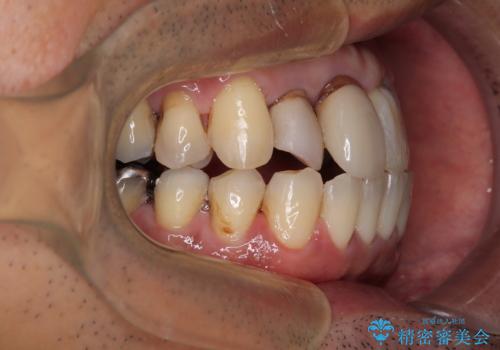

仕事柄海外出張が多いとのことで、インビザラインにて矯正治療を行うこととしました。

矯正治療後は、前歯や下顎の奥歯など、むし歯治療途中の歯をオールセラミッククラウンにて補綴治療を行うこととしました。

治療途中で海外に長期滞在することとなり、5年近く帰国することができなかったため、治療期間は非常に長いものとなりました。

内側に転位していた前歯は、矯正治療では治しきることができませんでしたが、幸いにもオールセラミッククラウンに置き換える予定であったため、希望通りの仕上がりとなりました。